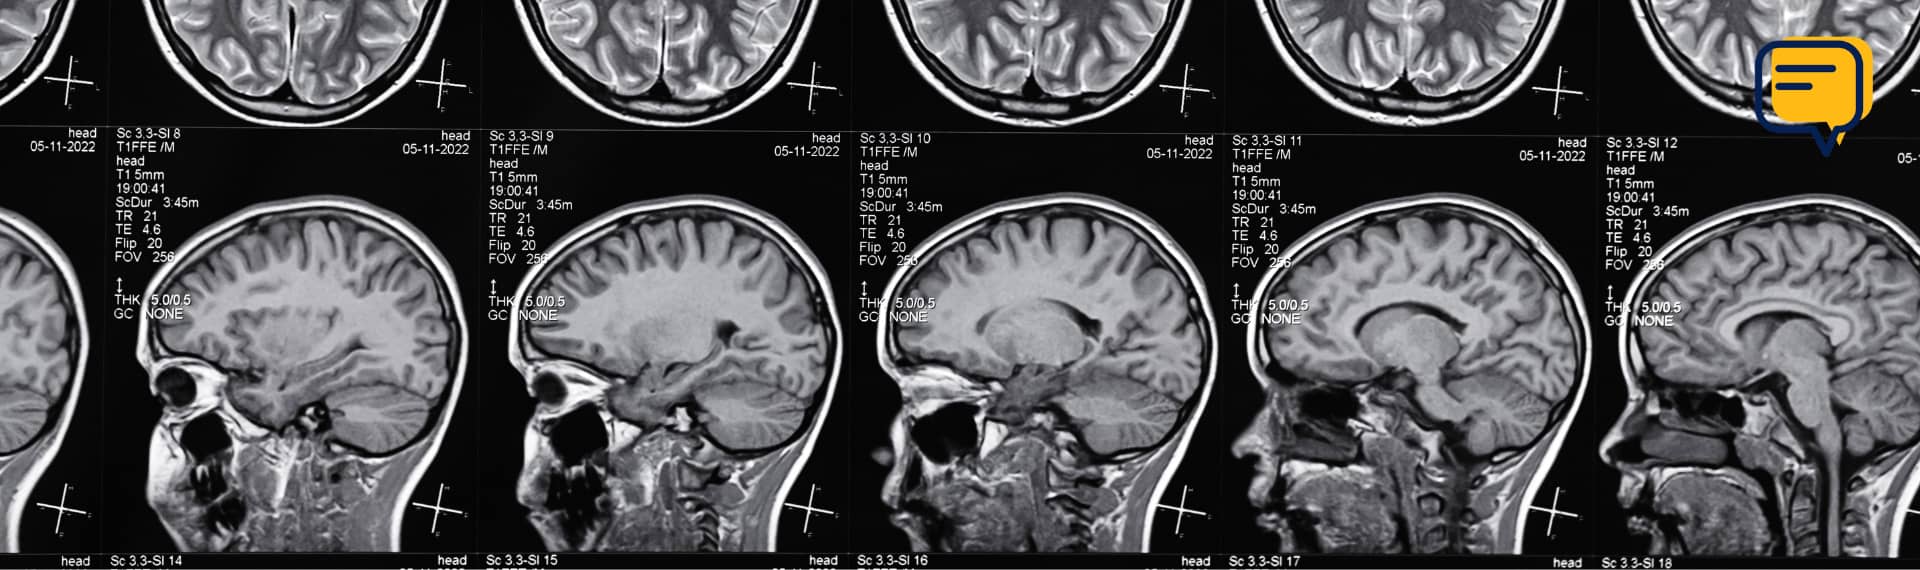

Behind the Images: A Look into Radiology with Dr. Eric Balle with radiology images

In this article, we take a closer look at diagnostic radiology through the lens of Eric Balle, MD, a postgraduate year 5 (PGY-5) radiology resident at Indiana University. Many students may recognize his name from our year-long ultrasound enrichment program or know his wife, Megan Balle, Ph.D., our Assistant Professor of Anatomy. Dr. Eric Balle’s story is a compelling reminder that your final specialty decision may not be the one you had in mind when you started medical school.

Radiology is one of the few specialties that is not part of the core clerkship experience in medical school, leaving many students with limited exposure to its scope. Diagnostic Radiology (DR) consists of a one-year internship followed by four years of residency. Many residents pursue an additional one- or two-year fellowship, with options ranging from neuroradiology to interventional radiology.

He describes radiologists as the "detectives" of medicine. With minimal clinical context, they use imaging—CT, X-ray, MRI—to identify disease processes, recommend further testing, and guide treatment. Every image offers a puzzle to solve, and no two cases are the same. That intellectual challenge is part of what continues to draw him to the field.